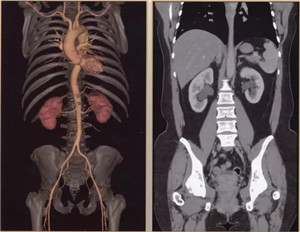

日前,辽阳市中心医院引进当今医学界最先进超高端的美国GE公司生产的Revolution CT(512层)正式投入使用,以此为标志,我市医学影像诊断技术进入超高清时代。该CT是当今世界上临床性能最为强大的CT,它以“合三为一、集大成”的特点引领着CT扫描领域在能谱、速度、宽度方面的国际潮流。落户于中心医院的该CT设备,是东北第三台,辽宁省第二台,目前中国医科大学附属第一医院、盛京医院尚无此种设备。

512层Revolution CT是目前业内探测器最宽、扫描速度超快、射线剂量超低、图像超清晰,且能进行能谱成像的后超高端CT,被称为“革命性”的CT。它实现了——

扫描范围最大:16厘米宽体宝石探测器,心脏、颅脑、肝脏等单器官检查一次扫描就可实现全覆盖;

图像分辨超清:0.23毫米的空间分辨率,对于2毫米冠脉支架的细节和支架内再狭窄清晰可辨;可超早期发现微小肿瘤病变。